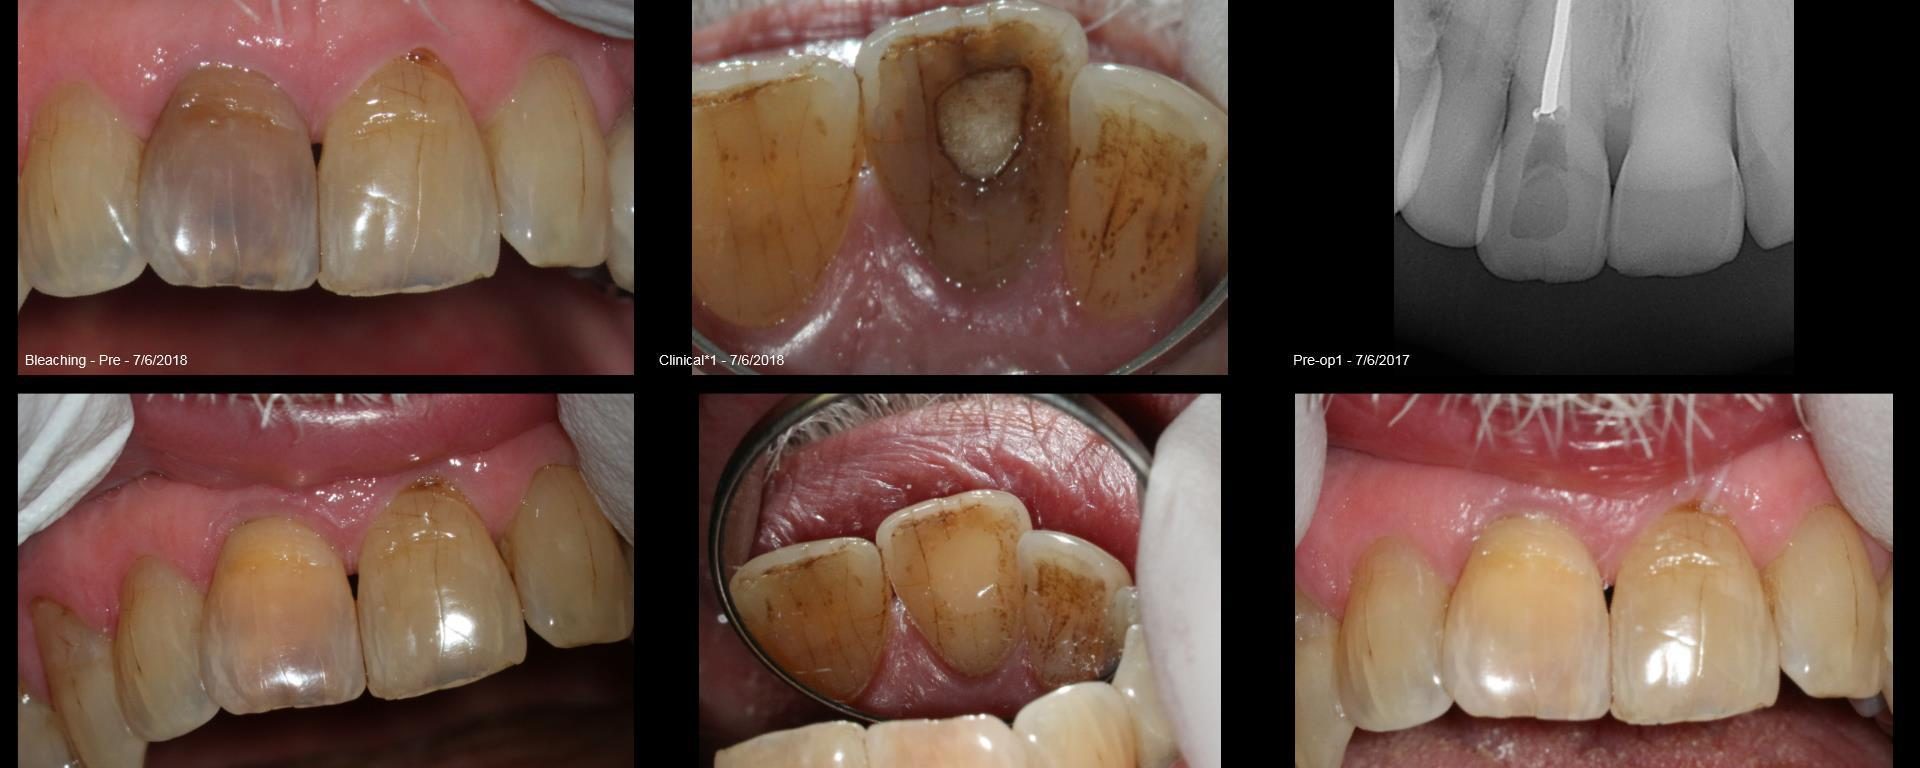

Non-vital Bleaching

July 27, 2018 4 comments

Tough very old discolored tooth. Previous RCT dome over 40 years ago. No pain, completely asymptomatic but just really bad color. Big shot attorney in DC. He was thrilled with the result.